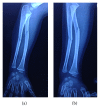

An Undescribed Monteggia Type 3 Equivalent Lesion: Lateral Dislocation of Radial Head with Both-Bone Forearm Fracture

Monteggia fractures are accepted as hard-to-recognize and easy-to-handle fractures. Adequate radiographic investigations and clinical examinations are necessities. This case holds unique features involving diagnosis and treatment. In this case, the radial head was dislocated laterally while both bones were fractured in the proximal diaphysis, being the first to be mentioned in the literature. Closed reduction of the ulna is the preferred method of handling and almost always results in reduction of the radial head. Literature obligates ulnar reduction as a preliminary to reduce and stabilize the radial head. Closed reduction reduced the ulna but the radial head was not reduced. Hence an intramedullary K-wire was used to reduce the radial head and a long arm cast was used to stabilize the reduction. The operation was successful and follow-up showed no complications.